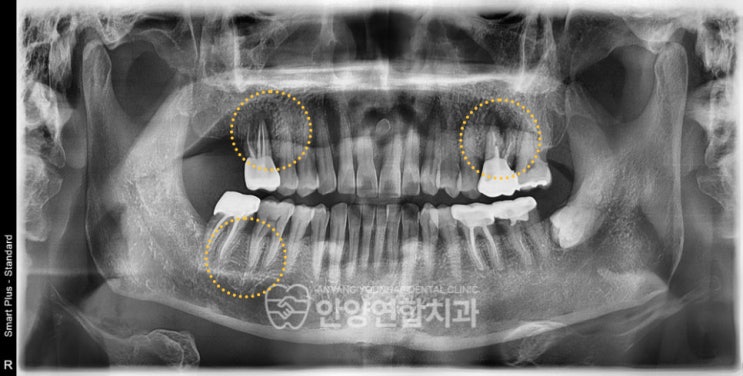

안양임플란트 치아정출예방까지 고려하는 치과에서

안양임플란트 치아정출예방까지 고려하는 치과에서 안녕하세요, 안양연합치과 대표원장 권영은입니다. 치아...